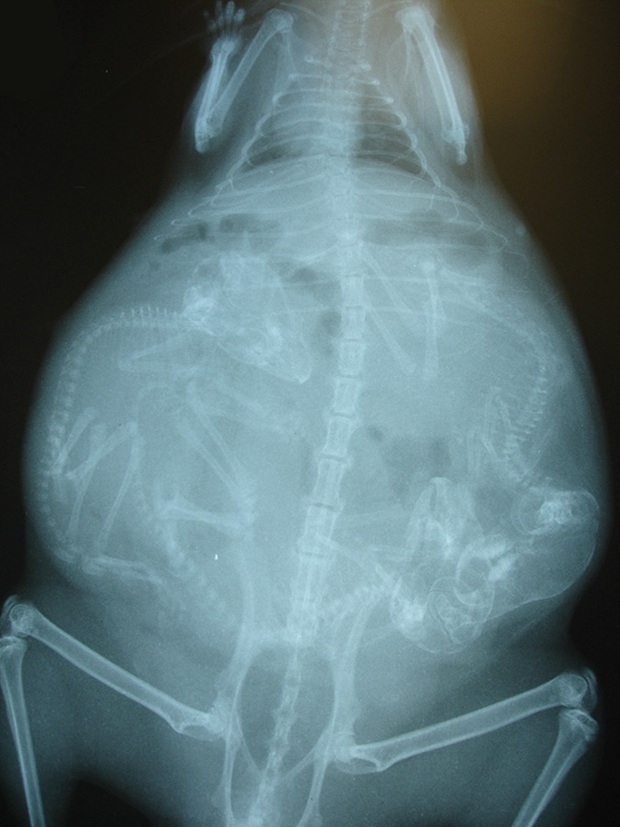

Ảnh chụp X-quang một con chuột lang đang mang thai.

Cận cảnh hình chụp X-quang một cô mèo đang mang thai và loạt ảnh động vật mang bầu khiến người xem rùng mình nhưng rồi thấy đẹp khó tả - Ảnh 8.